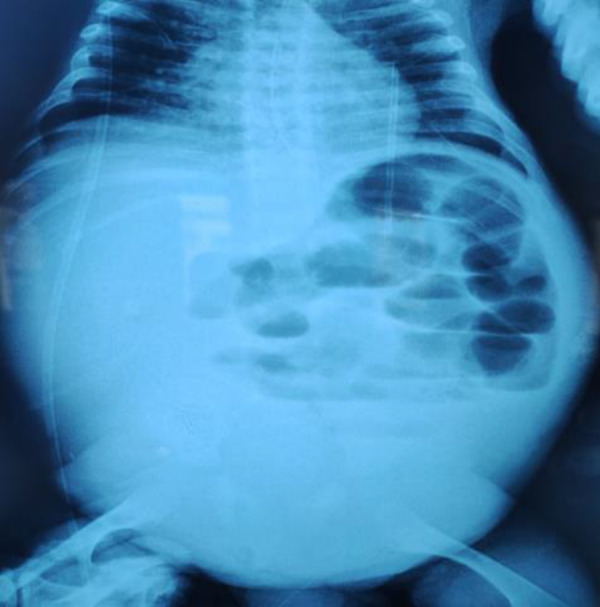

血栓栓塞事件是肾病综合征最严重但罕见的并发症之一。虽然外周静脉血栓和肺栓塞是最常见的,但肠系膜上动脉血栓形成是一种罕见但危及生命的事件。我们报告一例严重巨细胞病毒(CMV)感染并发先天性肾病综合征,导致肠系膜缺血。

Thromboembolic events are among the most serious, yet rare complications of nephrotic syndrome. While peripheral venous thrombosis and pulmonary embolism are the most common, superior mesenteric artery thrombosis is a rare but life-threatening occurrence. We present a case of severe cytomegalovirus (CMV) infection complicated by congenital nephrotic syndrome, leading to mesenteric ischemia.